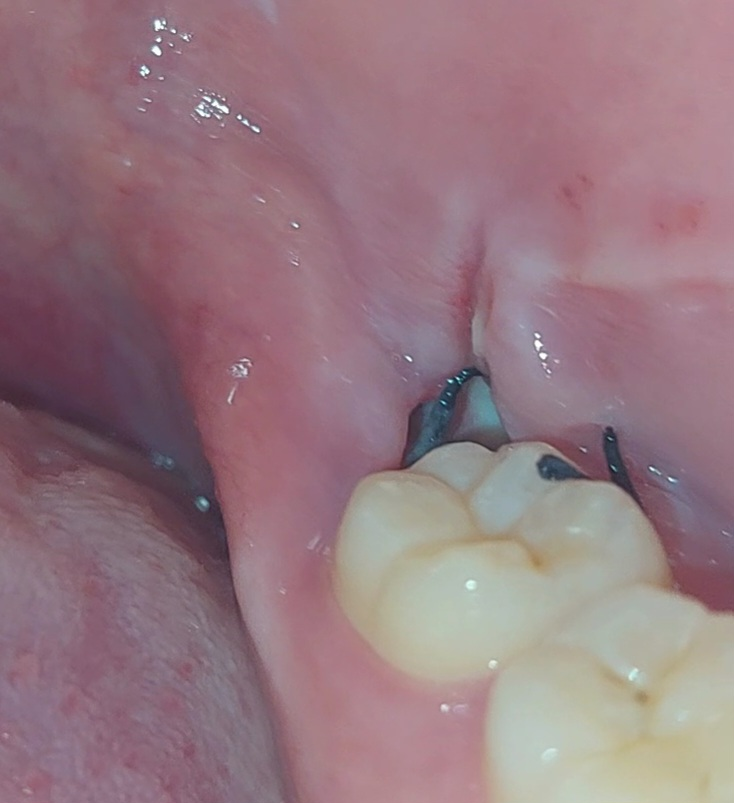

사랑니 발치부위에 웬 빵꾸가났어요. 깊이도 꽤 깊어요.

아래쪽 사랑니를 발치하고 5일차입니다

원래 발치부위에 혈병으로 가득차고 그렇게 아무는거로 알고있는데.

지금보니까 깊이도 꽤 깊고 안쪽은 회색을띄고있습니다.

계속 욱신거리고 진통제를 먹어야 안아플정도입니다.

채워진 혈병이 떨어져서 저렇게 된걸까요..?

• 1번 째 사진